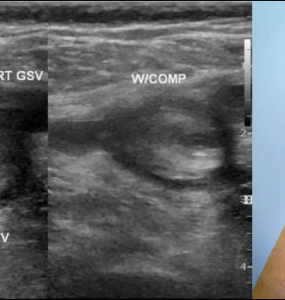

4 December 2025 by Shahriar Lahouti. CONTENTS Preface Epidemiology and Risk Factors Clinical presentation of PE Differential diagnosis Diagnostic evaluation D-dimer DVT Ultrasound for PE evaluation CTPA Diagnostic...